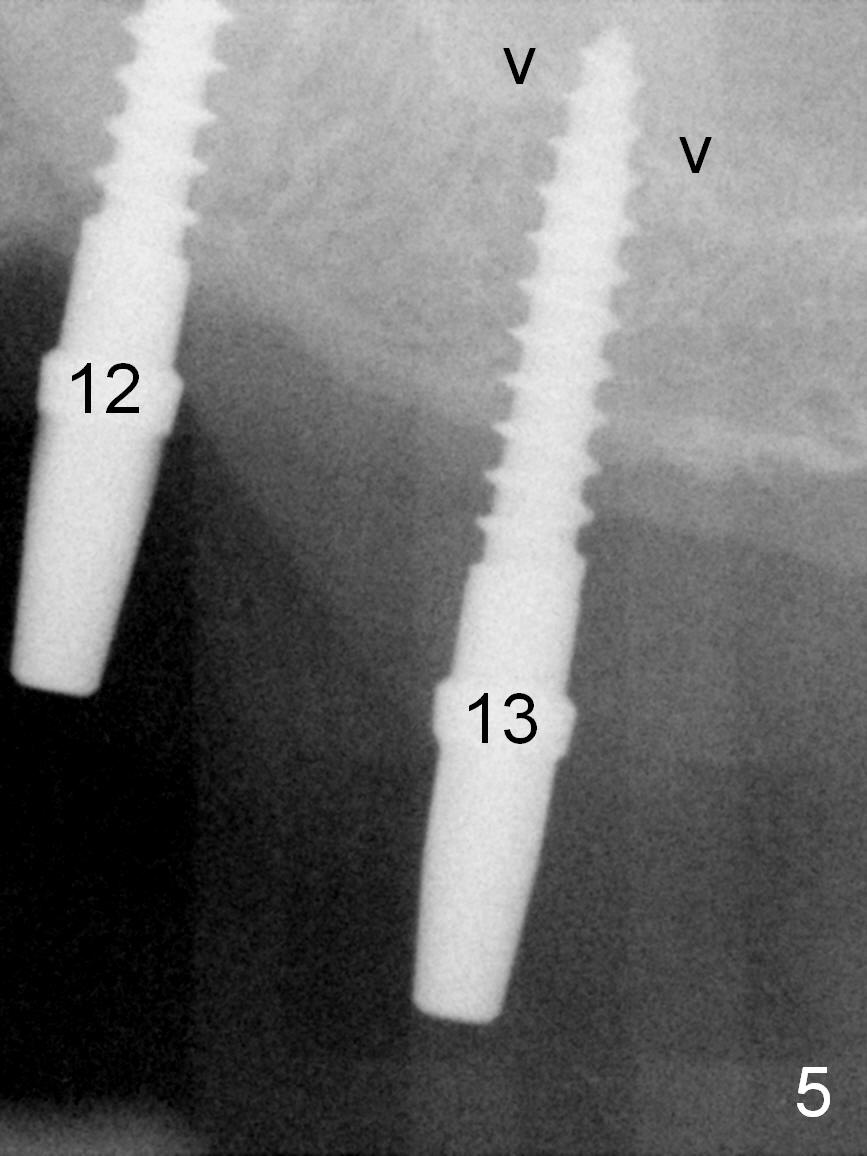

When the patient returns for implant placement (2nd visit after initial exam), he reveals that he is a dental phobic. He requests placement of 4 implants in the upper left quadrant, instead of 2. Narrow ridge is unexpected in the canine and premolar area (Fig.1). Limited bone height at #13 (Fig.3 arrowheads: sinus floor) is found when initial drills are in place (Fig.2,3). A 2-piece implant (4.5x17 mm tissue-level) is placed at #10 after extraction, while 1-piece implants are placed at 11 (3x17 mm (tissue-level, 15 °) and 12 and 13 (bone-level, 2.5x14, 12 mm, respectively; Fig.4,5). In fact the 1 piece implant at #13 is not completely placed (Fig.5). It is removed, the apical 3 threads are cut off (Fig.6 <, since a shorter implant was unavailable in the office) and the remaining implant is re-inserted. The insertion torques of the 4 implants are ~ 60, ~ 35, < 35 and 15 Ncm, respectively. After adjustment (Fig.7), immediate provisionals are fabricated at #10 and 11 (Fig.8, later splinted with composite), while perio dressing is applied around the implants at #12 and 13 and the provisionals at #10 and 11. There is no nasal hemorrhage postop. Although the perio dressing is loose 1 week postop (Fig.9), it is not removed. When the upper lip fissure (Fig.9 <) heals, provisionals at #12 and 13 are planned to be splinted to the other two ones. Two weeks postop, the upper lip fissure heals, the perio dressing dislodges and the implants at #12 and 13 are stable (Fig.10). After abutment height adjustment, a splinted provisional is fabricated over these 2.5 mm 1-piece implants (Fig.11).